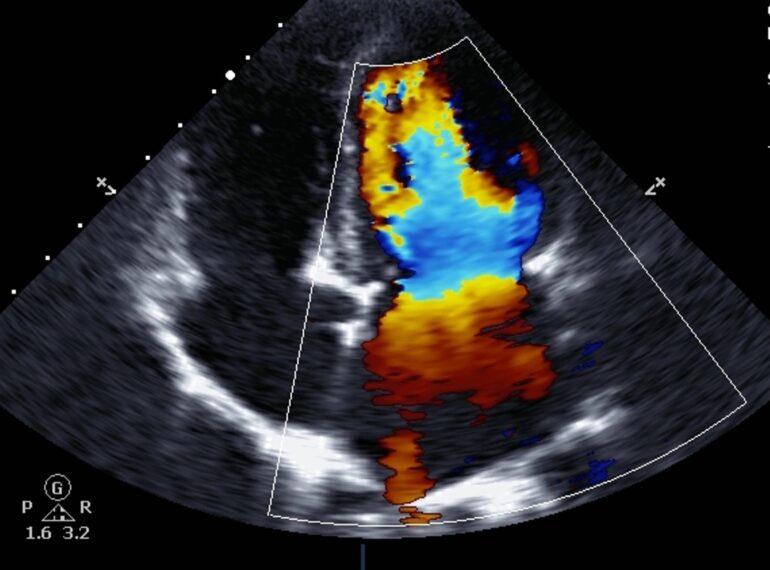

From primary angioplasty to complex stenting, receive expert treatment using the latest transradial techniques.

Precision Heart Diagnostics

Holter, Echo, TMT, and more—comprehensive diagnostics for timely and effective cardiac care.

Coronary Angiography

OCT/IVUS